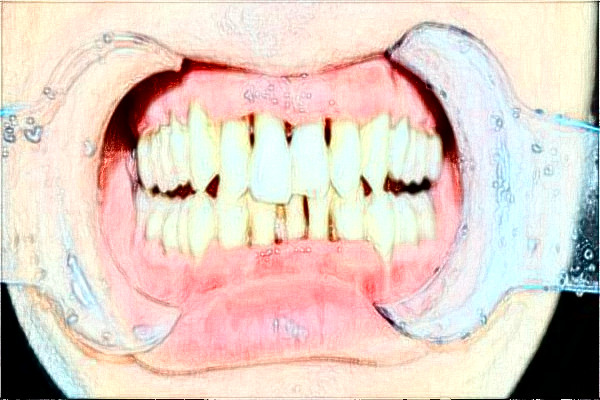

2024昆明43醫(yī)院口腔科案例

也許是因為對疼痛不是特別敏感,之前有過蛀牙的現(xiàn)象,聽別人說出現(xiàn)了蛀牙的時候是特別疼痛的,但是對于我來說并不是很疼痛,因此沒有太過重視這顆牙齒,也使這顆牙齒的蛀牙現(xiàn)象變得越來越嚴重,慢慢的這顆牙齒一塊一塊的就掉了,自從這顆牙齒開始掉的時候,吃東西就有一種異物感,吃完東西如果用牙簽來清理牙縫,感覺很不雅觀,于是就去了昆明43醫(yī)院口腔科找了醫(yī)生,醫(yī)生說因為殘留牙根的原因造成的,需要把殘留的牙根拔出來,然后醫(yī)生給我打了麻醉,就給我把牙根拔出來了,也許是因為打了麻醉的原因,在拔牙根的時候也沒有多大的不適感。